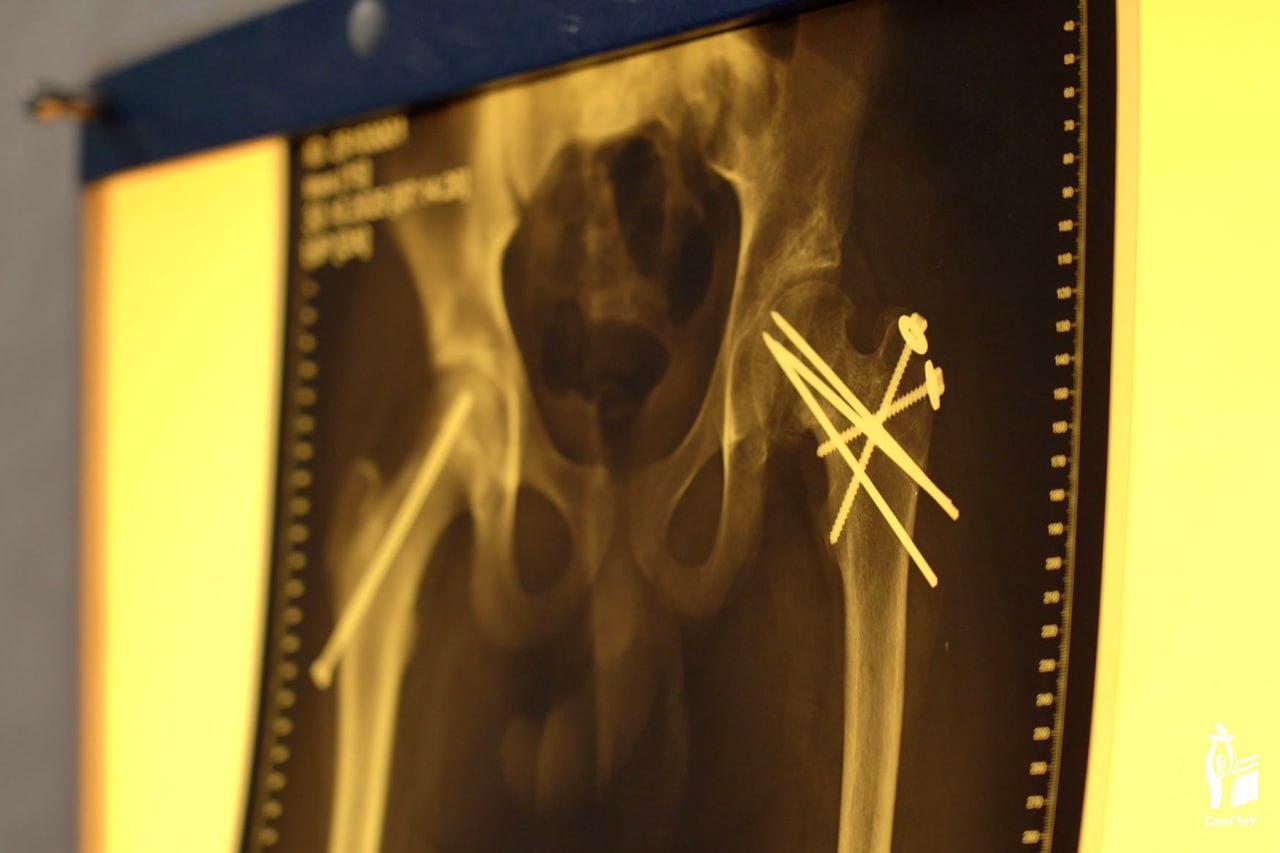

Состоялся заключительный этап лечения — хирурги удалили установленные на первом этапе металлоконструкции. После прохождения реабилитации подросток сможет полностью опираться на ногу.